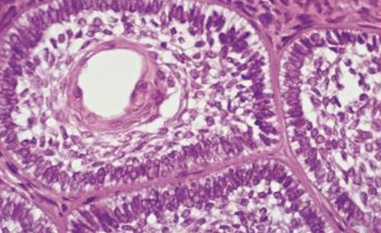

口腔病理學實驗

課程大綱